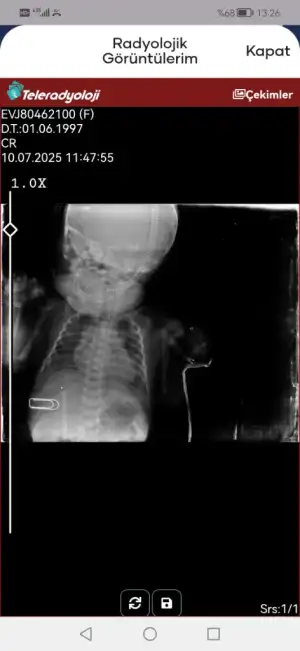

Eklentiler

• Screenshot_20250709_142908_tr.gov.saglik.enabiz.webp

Screenshot_20250709_142908_tr.gov.saglik.enabiz.webp

16,8 KB · Görüntüleme: 22

• Screenshot_20250709_011620_tr.gov.saglik.enabiz.webp

Screenshot_20250709_011620_tr.gov.saglik.enabiz.webp

14,3 KB · Görüntüleme: 14

Toparlıyor merak etmeyin. Doğumda oksijensiz kaldı mı?

Valla 10 sanyi sezeryan sırası gostrdiler agladgninduydum yogum bakima alalim dediler solunumunda biraz sıkıntı var sonra dediler zature olmus anlamadim solunuma bagli bebegm suan dualarinizi eksik etmeyin